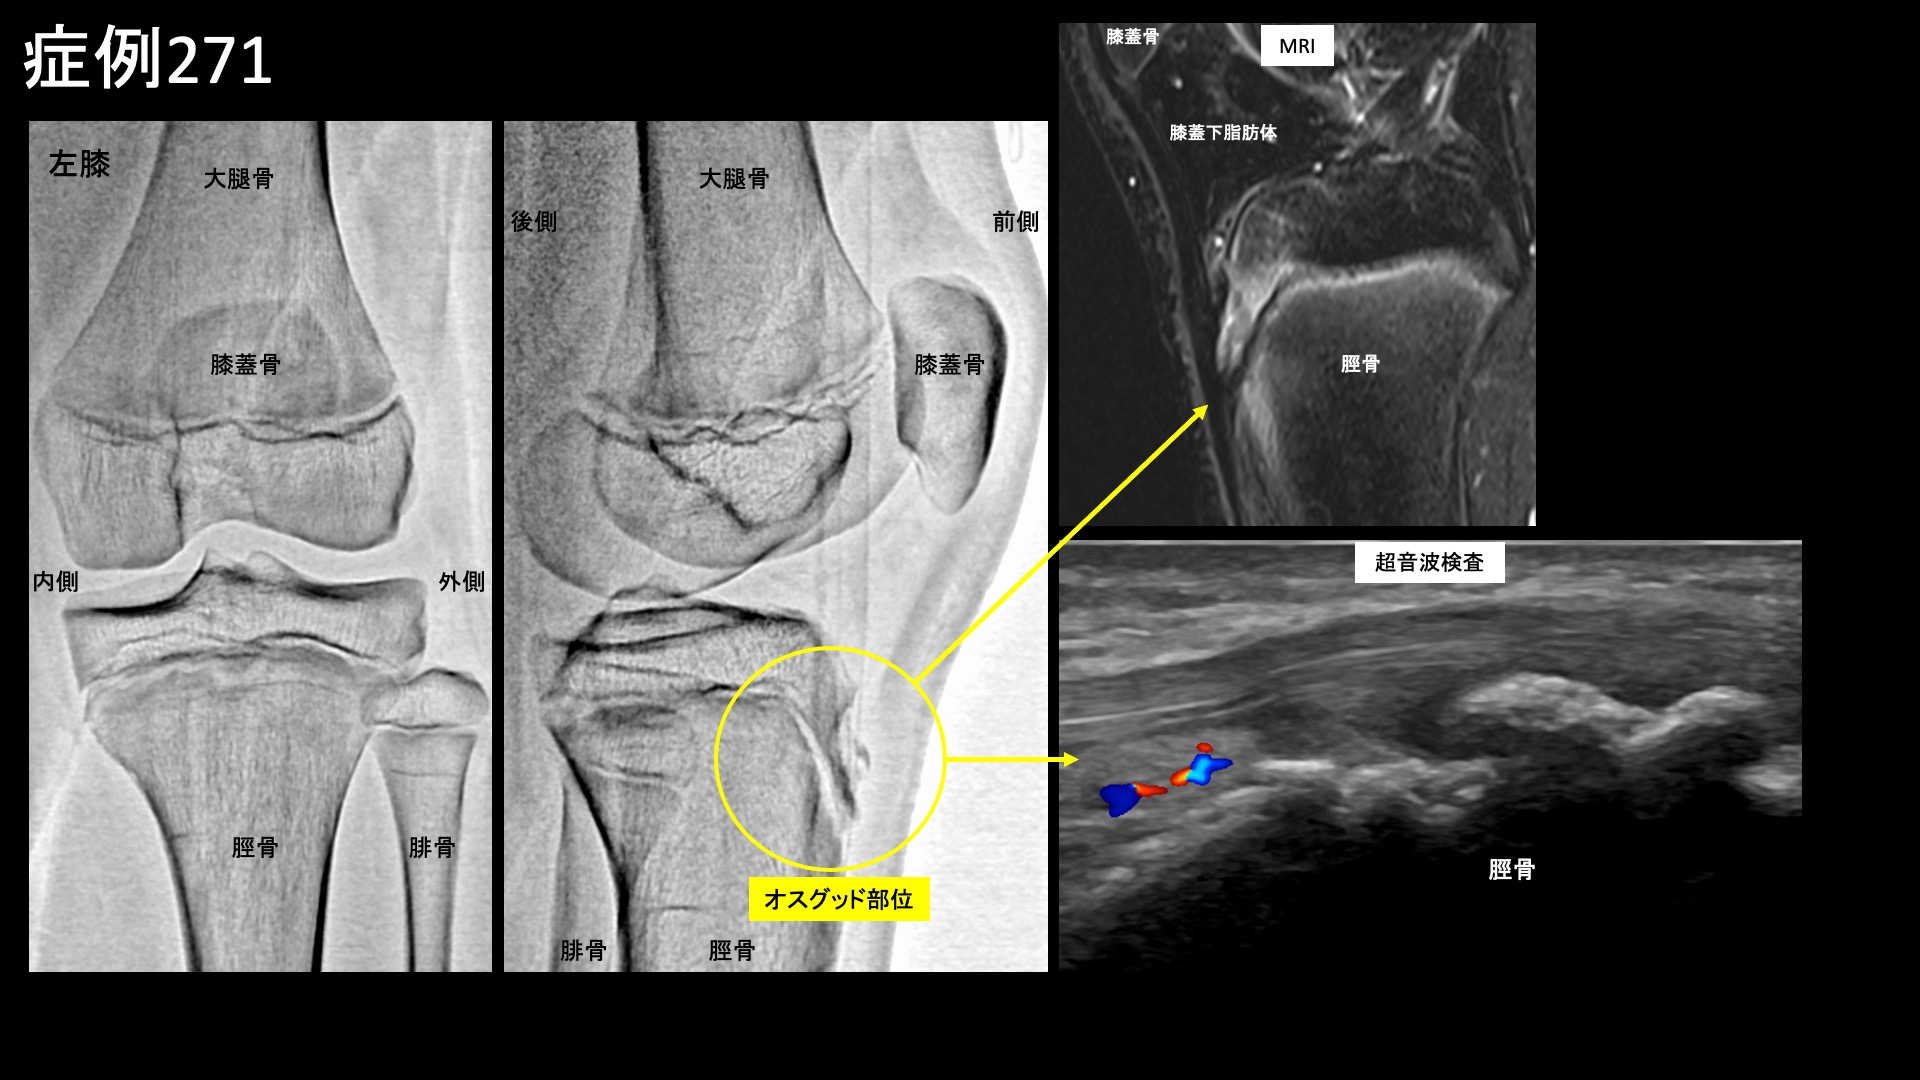

エコー検査では典型的なオスグッド病の所見であり、中等度の脛骨変形(骨形成過程での障害)、および周囲の異常血流信号(モヤモヤ血管を反映)を認めました。MRIでは同部位の炎症を反映して白く描出されました。膝蓋腱は保たれていたほか、右膝には異常所見はありませんでした。典型的なオスグッド病であり、治療適応と判断し、モヤモヤ血管(病的新生血管)に対する運動器カテーテル治療(微細動脈塞栓術)を受けていただきました。

血管造影を行うと、前脛骨反回動脈で同オスグッド部位(膝のお皿の下にある脛骨の先端部分(脛骨粗面))に一致して、モヤモヤ血管が濃染像として描出されました。治療後は画像上速やかに消失しました。その他複数箇所の治療を行い終了しました。

治療前画像:損傷を受ける、あるいは繰り返しのストレスにより発生した異常な新生血管

治療後画像:カテーテルを用いて塞栓物質を血管内に投与し新生血管を塞いだ状態